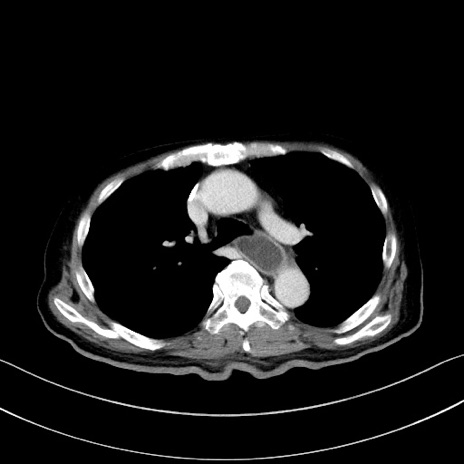

症例28(横断像)

【症例】60歳代男性

【主訴】嘔吐

【現病歴】胃癌にて胃全摘後。食思不振が悪化し、夜中に嘔吐することがある。

【既往歴】胃癌、胃全摘、脾摘、胆摘後

【データ】WBC 5900、CRP 10.56